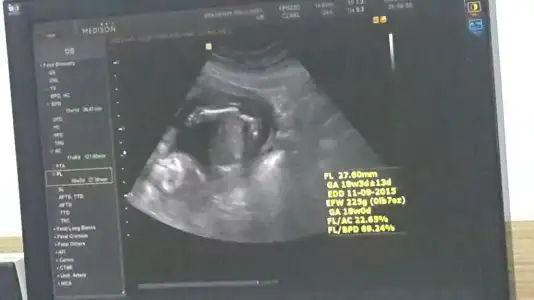

dr soylemeden siz gorun genital nub teorisi ( bebegin cinsiyeti)

Benim bebeğimin cinsiyeti konusundada bana yardımcı olabilirseniz çok sevinirim hanımlar :)

Bu bebiste erkek gibi geldi bana dikkatli bakinca cikinti var yukari kalkik paralel deil.. kac hagtalik sen ne hissediyorsun ??? Doktor hicmi yorum yapmadi

23 bitececek ccnm kizsada erkek sede benim hayatim o ama bir kesinlesmedi dunde erkek gibi dedi